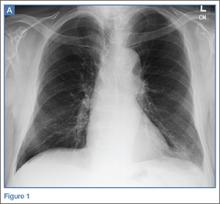

Radiographs and a noncontrast computed tomography (CT) scan of the chest were obtained. A representative posterior-anterior radiograph (Figure 1a) and a coronal noncontrast CT image (Figure 2a) are shown above.

The frontal chest radiograph demonstrated abnormal peripheral opacity at the left lung base (white arrow, Figure 1b), and the noncontrast chest CT demonstrated a peripheral, wedge/pyramid-shaped subpleural ground-glass opacity (white arrow, Figure 2b). Based on the persistent peripheral opacity despite treatment, and the patient’s clinical symptoms of acute sharp chest pain/hemoptysis, a pulmonary infarct was considered as part of the differential diagnosis, and a contrast-enhanced pulmonary embolism (PE) protocol CT was obtained for further evaluation. A coronal image from the contrast-enhanced CT demonstrated the wedge-shaped peripheral opacity (white arrow, Figure 3) as well as filling defects in the bilateral pulmonary arteries (red arrows, Figure 3), indicating the presence of PE.